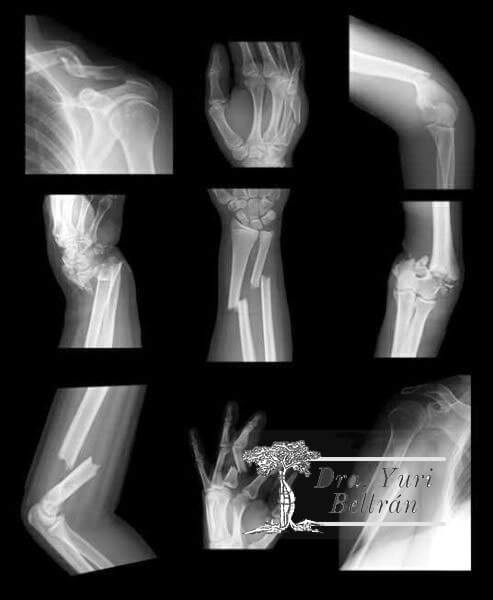

Necesito-cirugia-si-sufro-una-fractura-osea